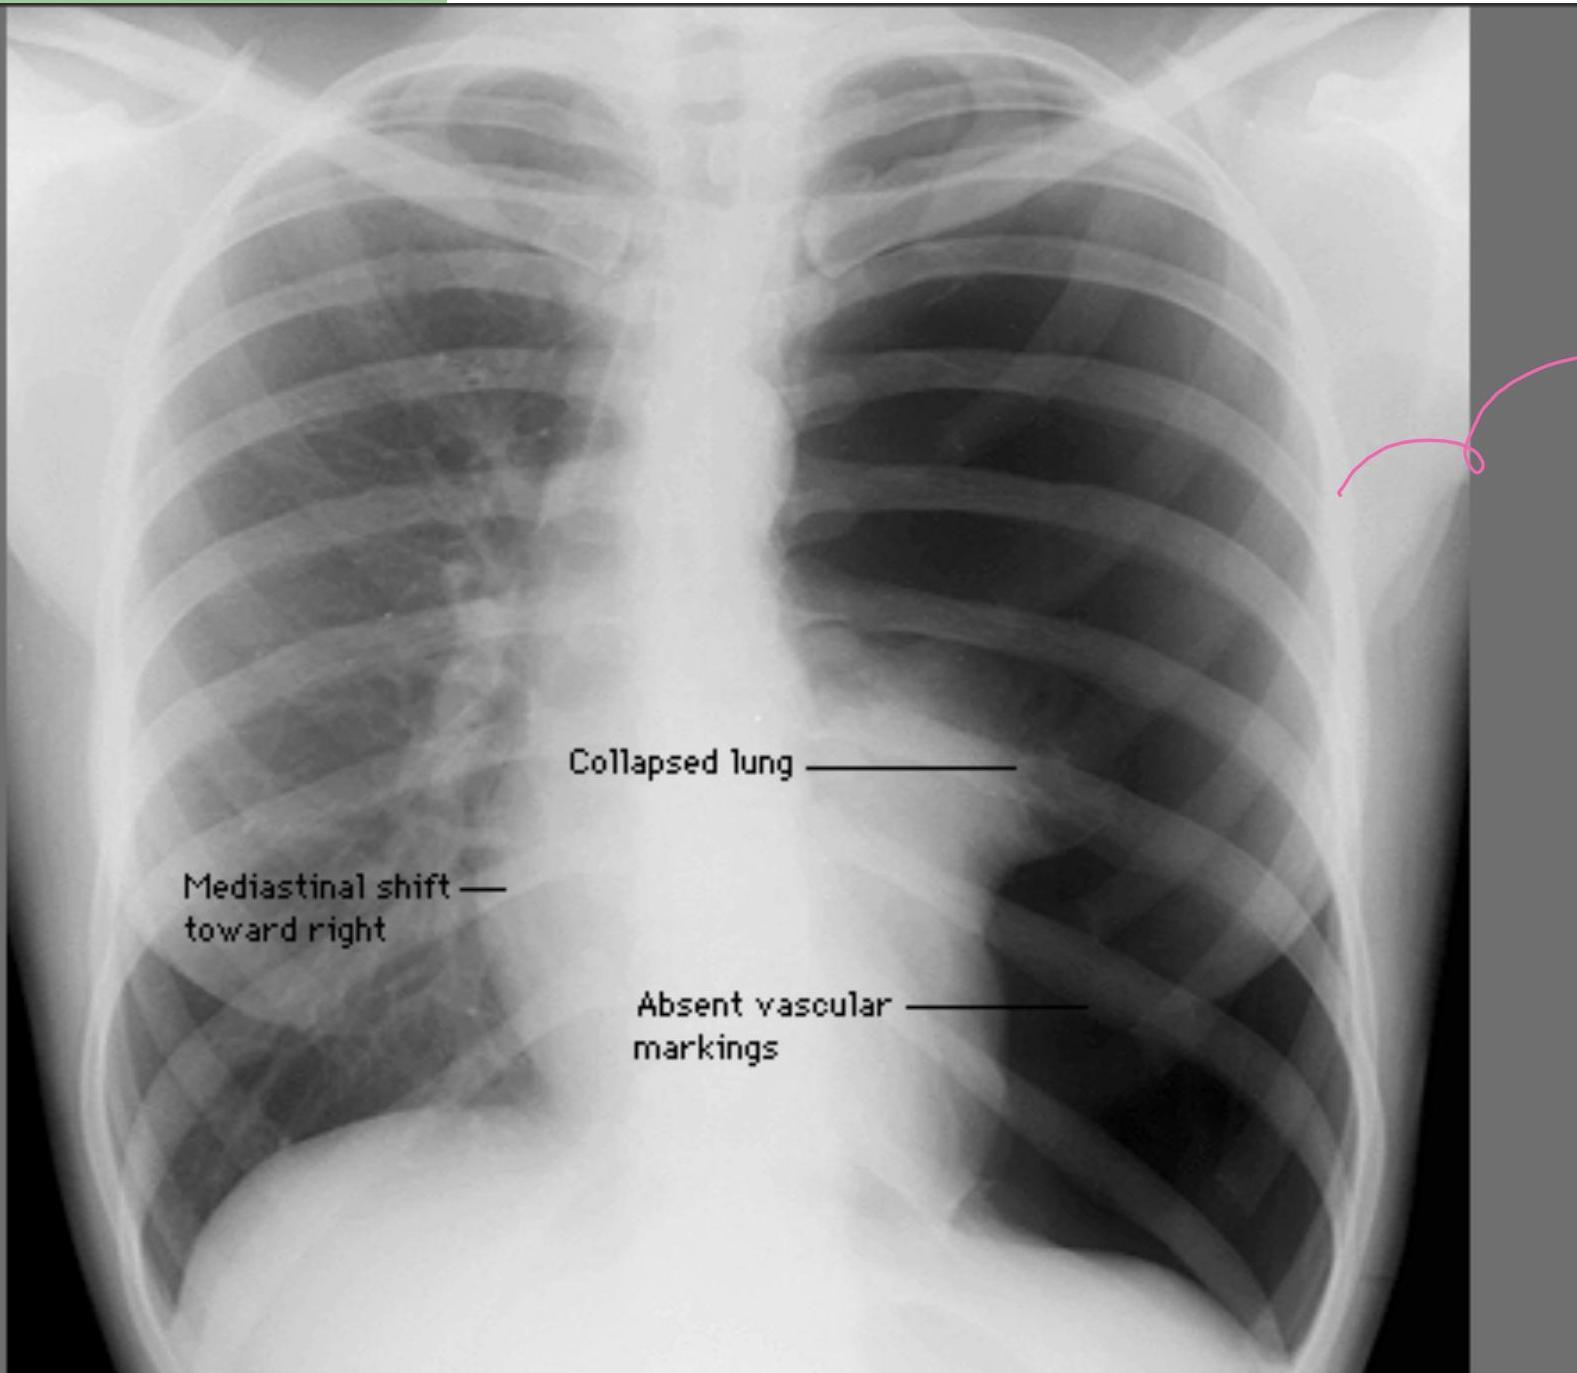

Tension Pneumothorax (Collapsed lung, Mediastinal shift, Absent lung markings):